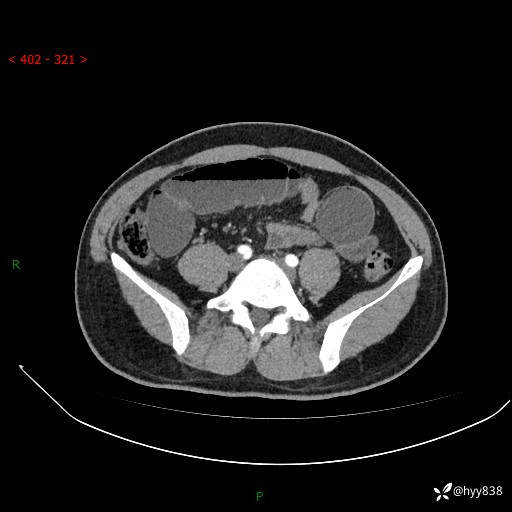

年轻男性,腹痛5月余。除了肠梗阻,你还能看到什么---结果公布~

主诉:腹痛5月余。

现病史:患者于5月前无明显诱因开始出现腹痛,上明显,为间断性胀痛不适,无畏寒发热,无心慌气促等特殊不适,遂来我院。我院门诊遂以“腹痛原因待查”收入我科。 起病以来,患者精神、饮食、睡眠欠佳,大小便正常。体力体重无明显变化。

腹部CT增强扫描(动脉期+静脉期)